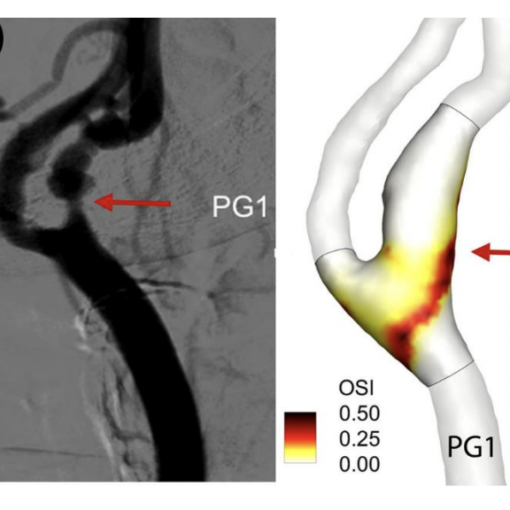

A success story. Our research activity focused on identifying quantitative indicators of electrical dysfunctionality through numerical post-processing of electro-anatomical maps [1]. Specifically, we found that an increase in slow-conduction corridors and pivot points characterizes disease progression: they stratify patients with episodes lasting less than seven days from those with a persistent form (see Figure 1). Our numerical simulations confirm the link between these indicators and arrhythmic propensity: an atrial substrate formed by severe slow conduction and pivot points enables localized reentries characterizing an AF episode to be self-sustained for longer than mild substrate characteristics [2].

Main clinical outcome. Our research let us connect arrhythmic propensity with electrophysiological indicators obtained by processing electro-anatomical maps. This approach provides a new direction for tailoring the ablation strategy based on the patient’s individual electrophysiological properties (see graphical representation of the whole process in Figure 2).